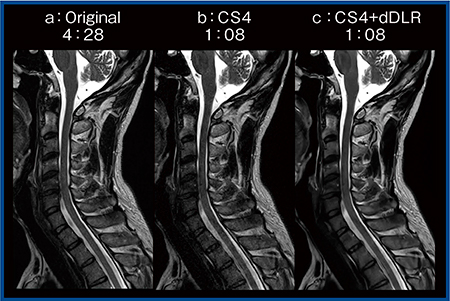

しかしながら,MeACSを用いてもアンダーサンプリングを行わない画像よりも画質は低下することから,dDLRを併用することで,短時間撮像を実現しつつ,さらなる画質向上を図ることができる。実際の画像(図3)を見ると,CS強度4+dDLRの画像(c)では,撮像時間が約1分と短いにもかかわらず,約4分半かけて撮像された画像(a)よりもノイズの少ない画像が得られている。

図3 MeACS+dDLRの効果(W.I.P.)